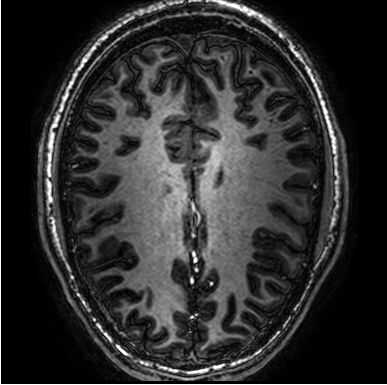

Creo que hay algo sobre una imagen que se generó teniendo cerebro 'rodajas' se imprime en rebanadas - jaja pero en plástico y no cerebro (aunque sería más fácil estudiar!).